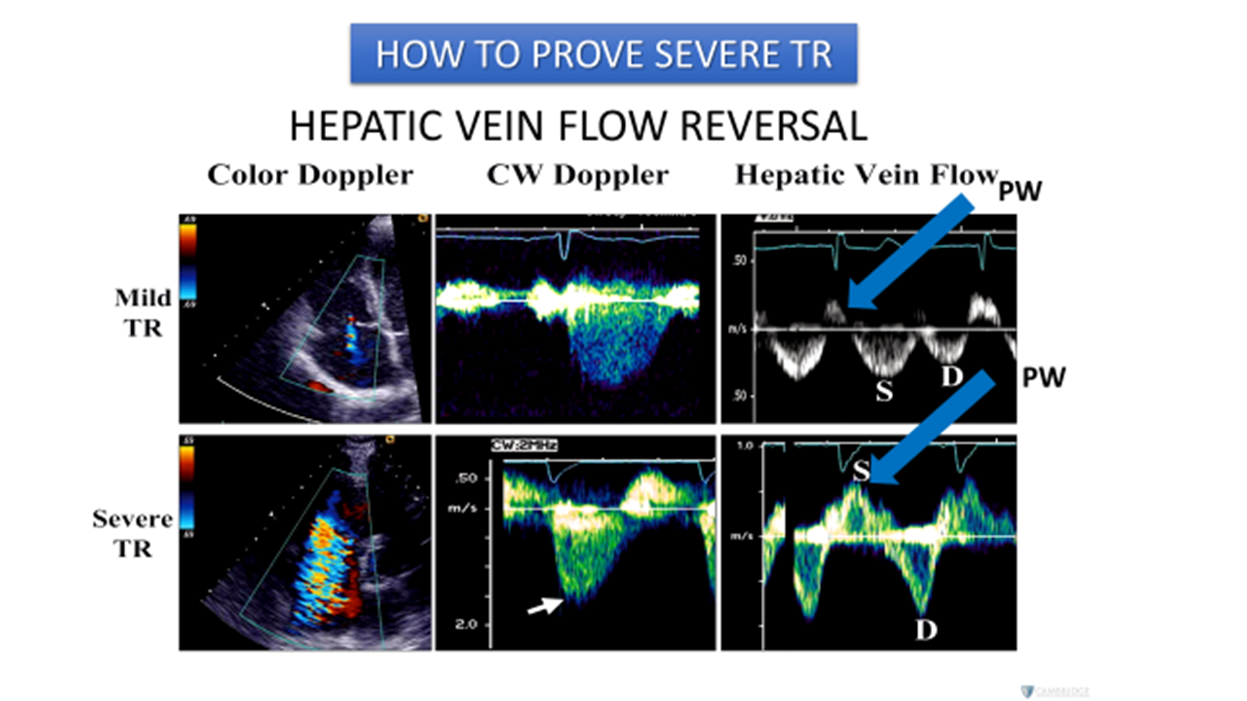

Normal hepatic vein flow travels _____ from the transducer towards the IVC and is encoded in _____

away/ blue.

TR flowing into the IVC & Hepatic veins will flow ______ the transducer during systole and is encoded in _____

towards/red

On the spectral waveform, this systolic flow will appear _____ the baseline (______)

(color & spectral flow reversal of the hepatic veins)

above/ antegrade

The hepatic vein waveform can be reflective of the ______

severity of TR present.

The more severe the regurgitation, the more _______ the hepatic waveform becomes.

pulsatile

anything above baseline means flow reversal

How to prove severe TR